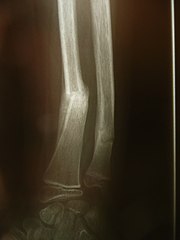

- Fracture healing - hematoma , granulation tissue, fibrous muscle, which turns into primitive skeletal muscle. Remodeling creates a definitive bone muscle.